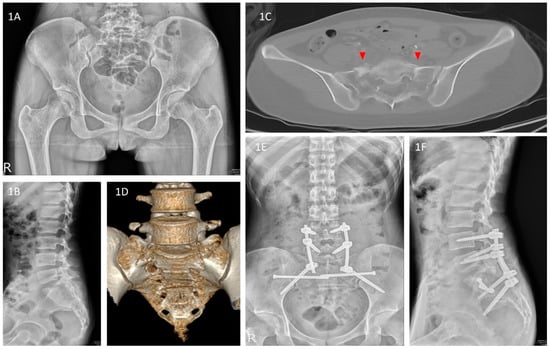

| Keshishyan et al., 1995 | Cross measurement method (Keshishyan Method) [14] | The measurement method described by Keshishyan et al. for assessing the displacement of pelvic ring continuity in children used only the AP pelvic view. Originally, this method was applied for skeletally immature patients and measures the distance from the inferior aspect of the sacroiliac (SI) joint to the contralateral triradiate cartilage. We used the modified method described by Lefaivre et al. to assess our adult patients. Observers were instructed to measure from the inferior SI joint (iliac side) to the inferior aspect of the teardrop in the AP pelvic view. “Y” was the length from the left SI joint to the right teardrop, and “X” was the opposite. Observers were instructed to measure the distance using the measuring software. We then calculated the ratio (X/Y) to standardize the baseline of comparison of the displacement (Figure 4). |